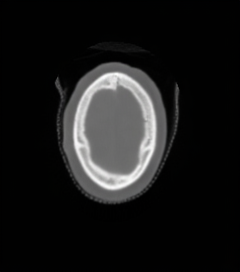

CT Scan